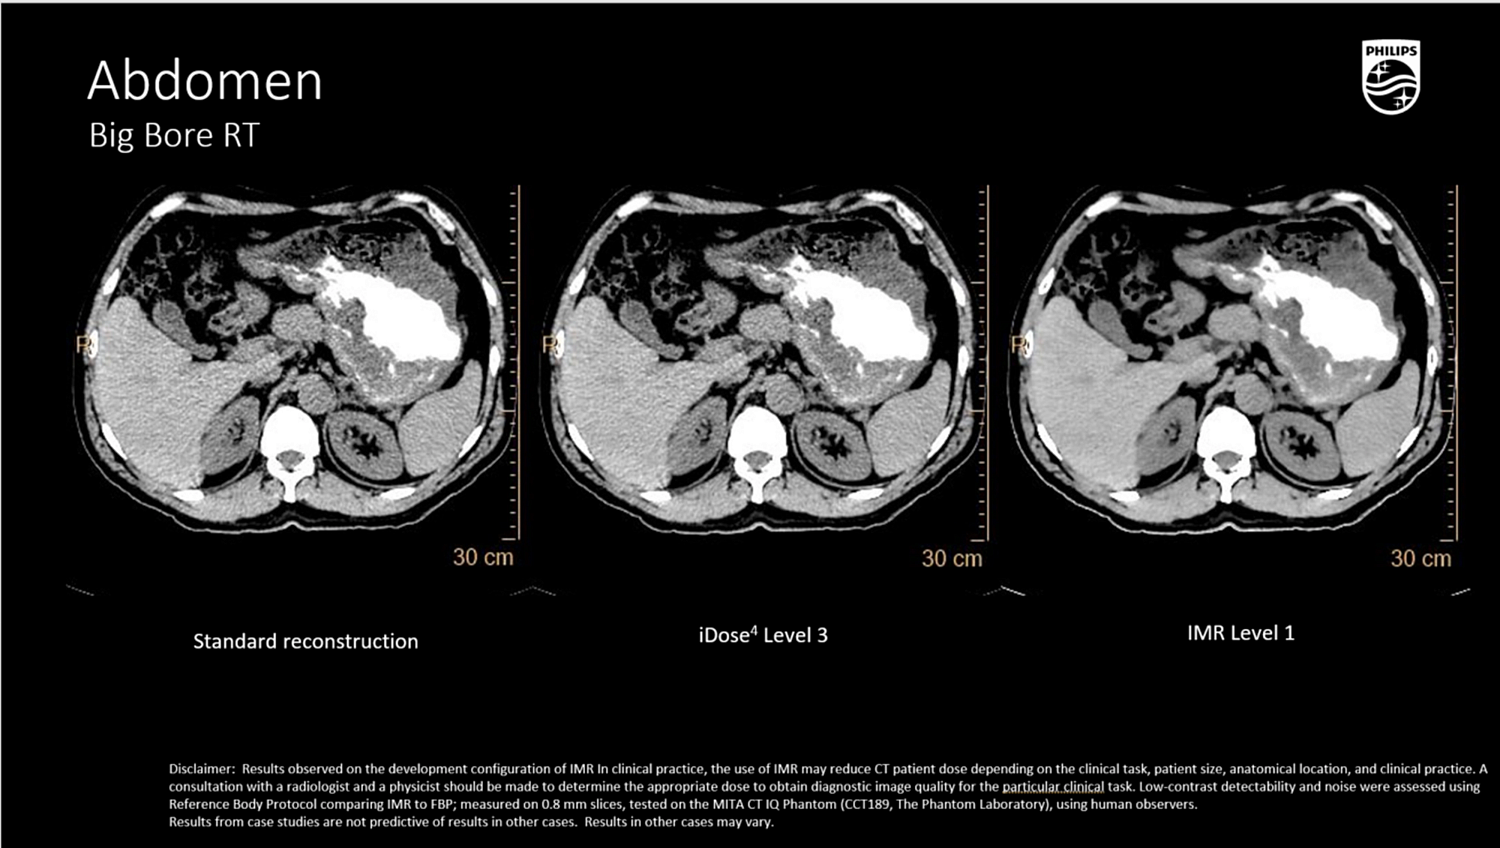

Клинические изображения

iDose⁴ (Iterative Dose Reduction Technology)

- Гибридная итеративная реконструкция в проекционном и изображен ческом пространстве повышает качество изображения и устраняет артефакты.

- Повышает контрастно-шумовое соотношение (CNR), снижая лучевую нагрузку на 50–80% при сохранении пространственного разрешения

Абдоминальная и тазовая локализация

- Визуализация мягкотканных опухолей (печень, почка, поджелудочная железа, органы таза) с контурированием OAR,